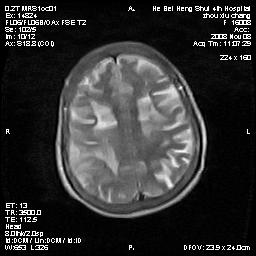

标题: MRI1883:女67岁,半年前曾患脑梗塞,治疗后好转,近3各月精 [打印本页]

女67岁,半年前曾患脑梗塞,治疗后好转,近3各月精神恍惚。

两种可能:1,转移瘤,2,脑炎,建议增强扫描

形态及整体病灶看起来首先考虑转移瘤或淋巴瘤,但奇怪的是多个病灶周围均未见显著的水肿区,这不符合这两个肿瘤的特点,结合ct表现及患者病史有个人考虑是否有皮层下动脉硬化性脑病伴多发胶质增生可能.

不像占位性病变,考虑脱髓鞘改变

皮层下动脉硬化性脑病伴脱髓鞘改变!